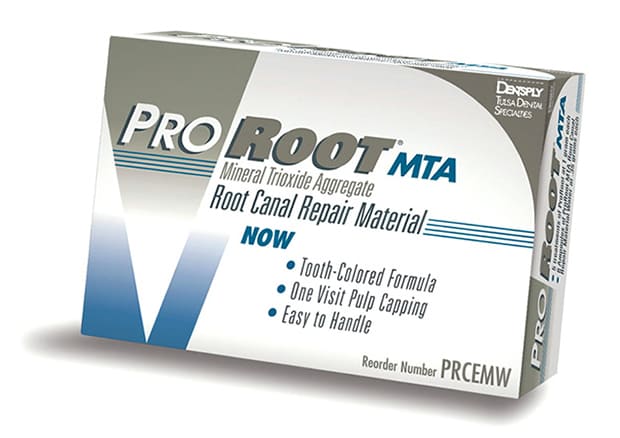

3.マイクロスコープによるMTAセメント根充

マイクロスコープにより感染物質を除去後の空洞には、MTAと言う歯科用セメントを使用して根充します。またこの根充の時もマイクロスコープを使用することが精密さを増します。

MTAは、強アルカリ性で高い殺菌効果と硬組織修復作用があるため、根管内の無菌化精度の向上と根管の密封により再発リスクの軽減が可能となります。

MTAセメントはまだ日本国内では保険適用されておらずコストがかかる充填材ですが、予後がとても良い材料になります。

MTAセメントによる根充

すべてのMTA根充にマイクロスコープを使用します

このときの根管充填で「MTAセメント」を使用することがポイントです。

「MTAセメント」には殺菌作用や強い接着性があり、歯と一体になる再石灰化性があるので、根管治療の成功率を高めます。

MTAセメントとは?

- 特徴 1

- MTAセメントは歯質接着性があるため、歯に対して機械的、化学的に接着することが出来る。

- 特徴 2

- MTAセメントは固まる際にわずかに膨張する性質があり、隙間なくしっかり密封させる封鎖性に優れている。

- 特徴 3

- MTAセメントは固まると強度が増し歯に適切な硬さになる。

- 特徴 4

- MTAセメントは固まると強アルカリ性を示すようになり高い殺菌性を発揮する。

- 特徴 5

- MTAセメントは固まると生体親和性が良い。

- 特徴 6

- MTAセメントは高い親水性を持つため、ガッタ・パーチャポイント使用時のように完璧に乾燥した状態でなくても使用が可能。

- 特徴 7

- MTAセメントには持続的に少しずつ水酸化カルシウムを放出するので、吸収されてしまった歯の根や周囲の骨の再生を促す。